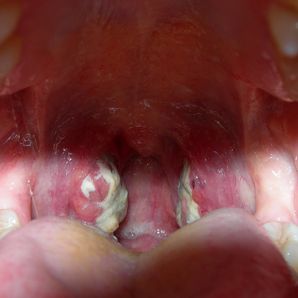

Amigdalita Cauze Simptome Si Tratamente Secom Ro

Stafilococ Auriu In Gat